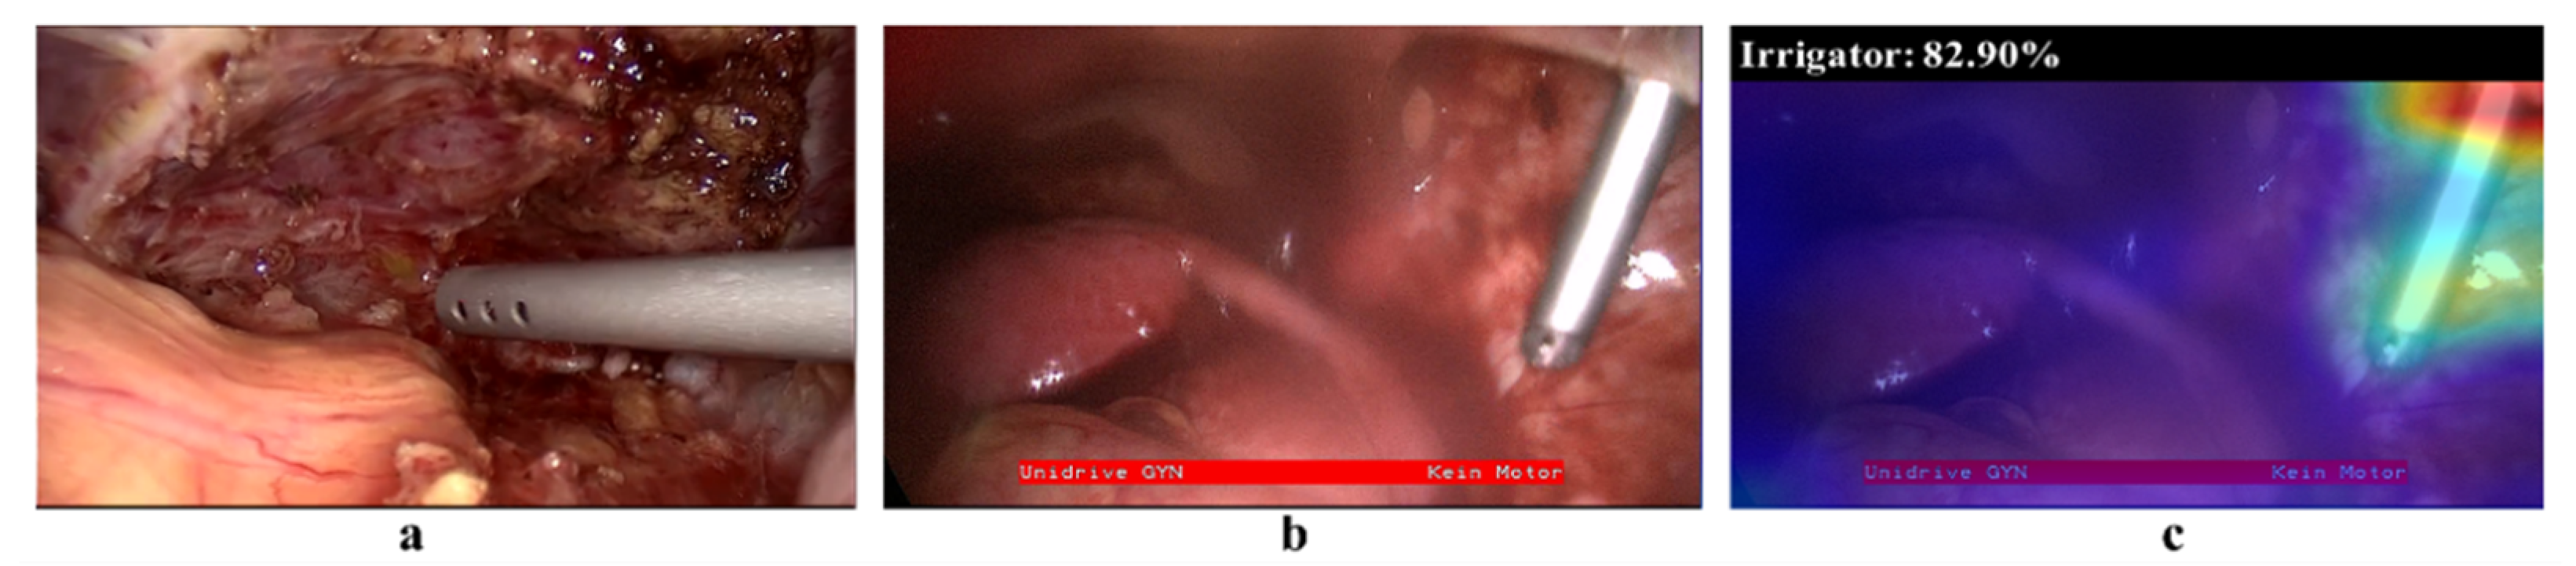

- Selvaraju, R.R.; Cogswell, M.; Das, A.; Vedantam, R.; Parikh, D.; Batra, D. Grad-cam: Visual explanations from deep networks via gradient-based localization. In Proceedings of the IEEE international Conference on Computer Vision, Venice, Italy, 22–29 October 2017; pp. 618–626. [Google Scholar]